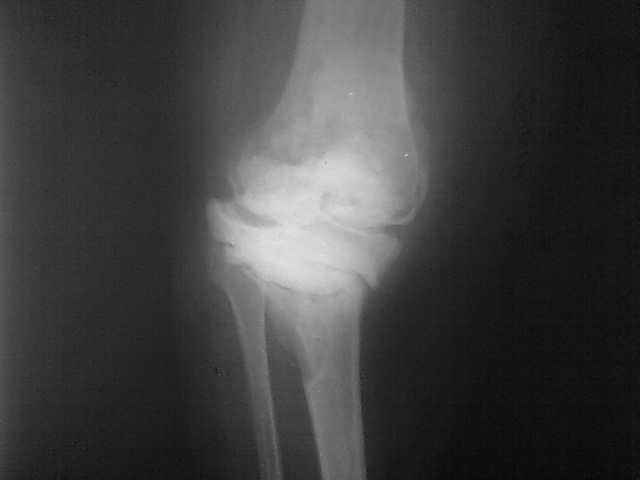

Уважаемые коллеги, прошу Вашего совета по тактике лечения. Женщина 1952 г.р., оперирована в 2006, в одной клинике установлен эндопротез правого коленного сустава, через год нестабильность обоих компонентов, доктор выполняет ревизию обычным протезом с задним стабилизатором. В октябре 2008 - нестабильность, свищ. В другом стационаре все удалено, спейсер с гентамицином, длинный курс антибиотиков. Коллатеральных связок нет. Собственная связка надколенника цела. До удаления протеза - выраженная смешанная контрактура. Сейчас свищей нет, анализы в порядке.

Планы: Стоит выбор 1) Обычный hinge с цементными ножками, вставками под тибиальным и бедренным компонентами с импакционной костной пластикой аллокостью с применением сеток для удержания трансплантата на tibia; 2) Онкологический hinge - с замещением проксимальной голени и сохранением бедра; 3 - артродез.

Мне очень хотелось узнать мнение коллег на предмет - если ставить простой hinge с костной пластикой - стоит ли использовать только костную крошку или необходим структурный костный аллотрансплантат? Есть ли у кого-то положительный опыт таких операций? Душа у меня не лежит использовать онкологическим протез для голени, т.к. пациентка слишком молода и сохранена собственная связка надколенника.

Артродез тоже потребует определенных усилий. Костный дефект очень большой....